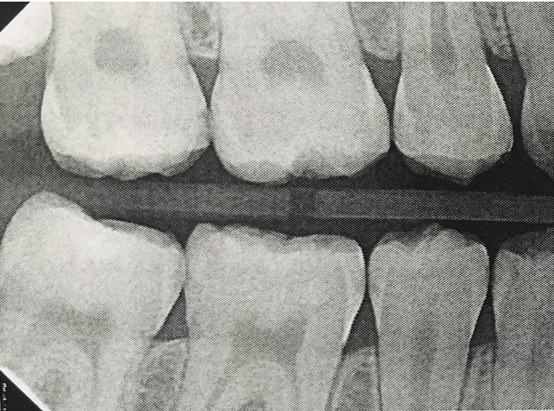

Fig 3. Three thin soft dental picks were used simultaneously for SDF proximal surface saturations in a teenaged patient (Fig 3). After 60 seconds, the treated regions were covered with 5% fluoride varnish (Fig 4). A comparison can be seen of pre-SDF-treatment bitewing films (Fig 5) and 8-month post-SDF bitewing films (Fig 6) for the patient shown in Fig 3 and Fig 4. Radiolucencies were similar or improved, except for contact of maxillary first and second molars.

Fig 6. Three thin soft dental picks were used simultaneously for SDF proximal surface saturations in a teenaged patient (Fig 3). After 60 seconds, the treated regions were covered with 5% fluoride varnish (Fig 4). A comparison can be seen of pre-SDF-treatment bitewing films (Fig 5) and 8-month post-SDF bitewing films (Fig 6) for the patient shown in Fig 3 and Fig 4. Radiolucencies were similar or improved, except for contact of maxillary first and second molars.

Figure 6

Interproximal insertion of SDF is demonstrated in different patients in Figure 3 through Figure 11. Various diameters and brands of soft dental picks may be used depending on the closeness of the proximal surfaces and ease of insertion; for example, some picks are designed for use in wider spaces between teeth. This protocol also offers versatility. Figure 3, for example, shows the simultaneous use of three thin soft dental picks to saturate proximal surfaces with SDF in a teenaged patient; the treated regions were subsequently covered with fluoride varnish (Figure 4). This patient was initially treated in April 2019 (Figure 5), with an identical re-application 3 months later. As shown in Figure 6, the December 2019 bitewing film revealed good results with the possible exception of the contact regions of the maxillary first and second molars. New SDF application was completed in the December appointment.

The senior author's (TPC) private practice experience with soft-tip insertion of SDF into contacting proximal surfaces of teeth is that most beginning proximal surface caries lesions cease to progress, as evidenced by subsequent bitewing radiographic comparisons (Figure 3 through Figure 6, Figure 12 through Figure 18). The chances for success vary, however, depending on frequency of application, subsequent flossing by patients or adults flossing younger children, diet control, individual mouth chemistries, and use of fluorides for the topical effect. It must also be emphasized that office staff should make extensive efforts to inform children and parents that subsequent daily flossing is needed to accompany SDF treatments; otherwise, SDF applications will only delay the inevitable progression of caries. Flossing methods should be demonstrated for patients and for parents so they may see how to floss younger children. Showing them enlarged graphic photographs of flossing results may be helpful in this regard. Parents and patients should be made aware that if interproximal dental plaque accumulations persist without daily interruption by flossing, the acid insult will eventually take its toll on the proximal surfaces and caries lesions will progress to the point where restorative intervention may be required.